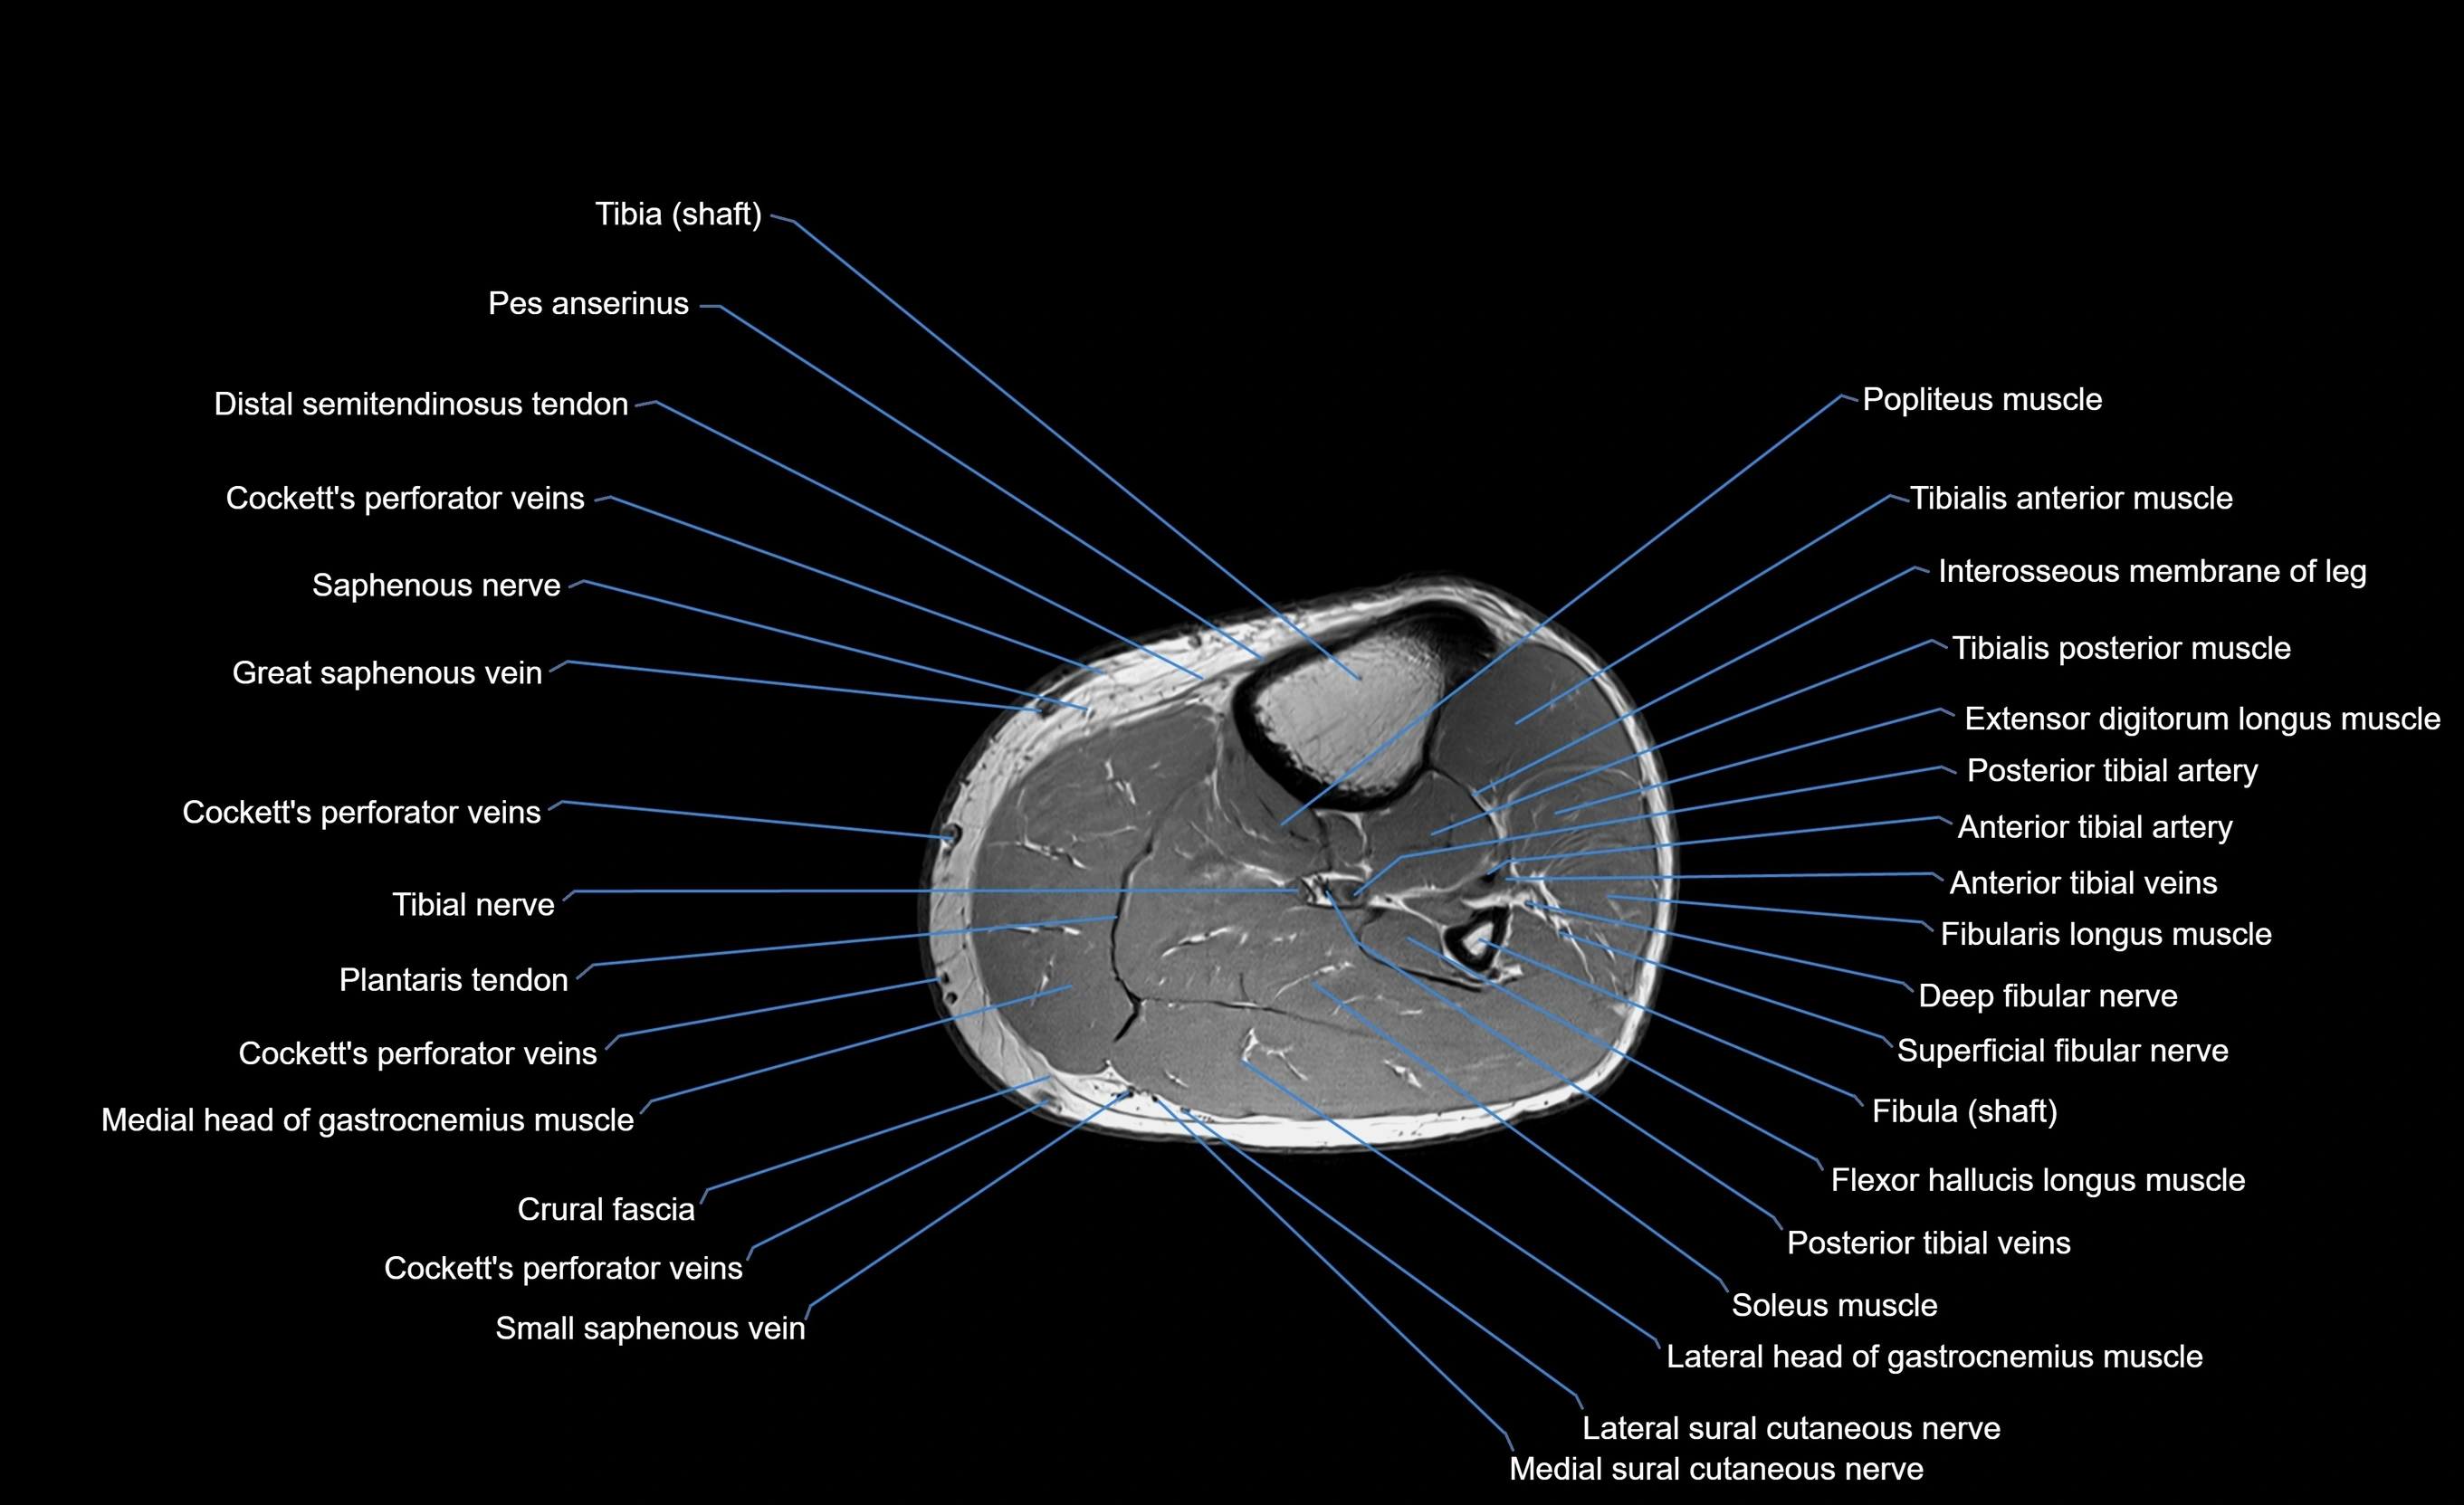

MRI image